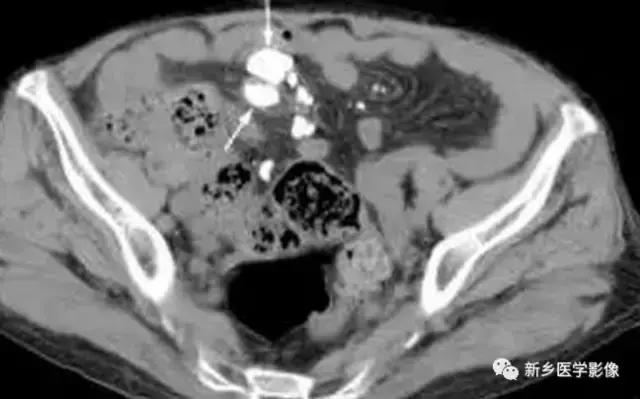

钙化的肠系膜淋巴结

主要表现为腹腔内弥漫性的小的、多发的钙化。大小可不一致。